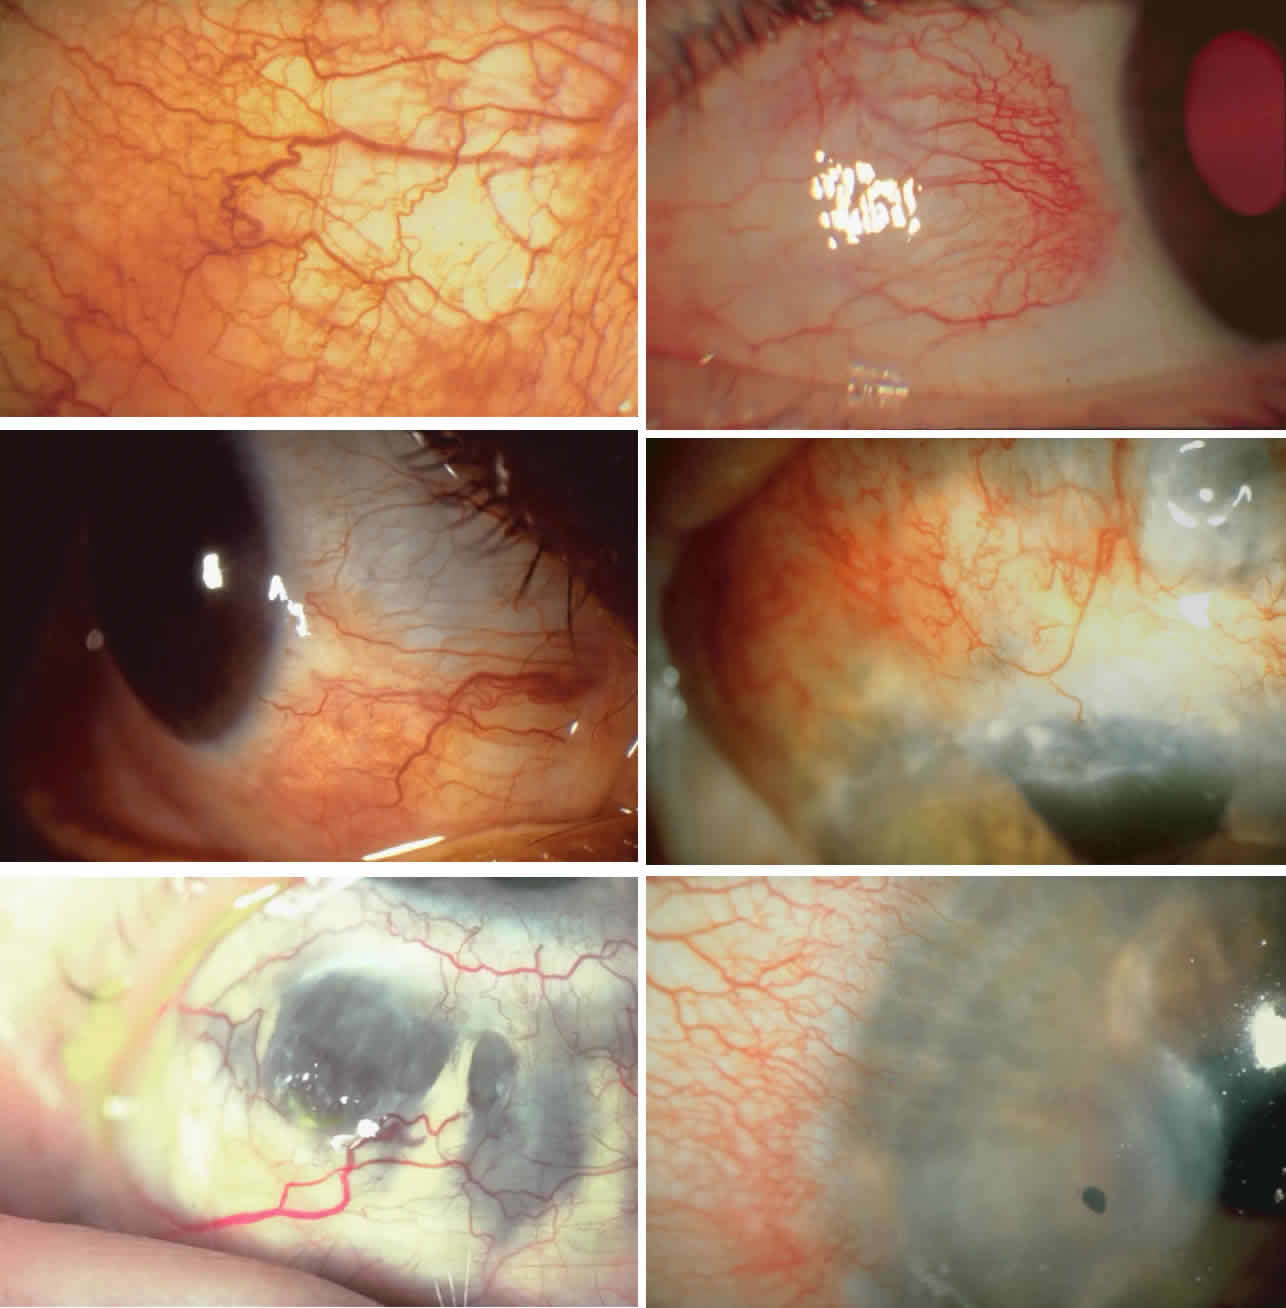

The inflammation of the eye is a prominent feature. The inflammation has

a bluish-red hue in contrast to the brighter red of episcleritis and

may be sectorial or diffuse. The severity of inflammation seems to depend

on the amount of episcleral tissue present. Therefore, it is more

prominent in younger people and is least prominent in those with rheumatoid

arthritis in whom the episcleral tissue almost disappears. Each of the various types of scleritis can be distinguished by its typical

clinical appearance. Because the pathologic change is in the sclera, there

is always edema and/or necrosis of that tissue. This gives rise

to an overlying episcleral edema and to congestion that may be very

severe and may need blanching with epinephrine 1:1000 or phenylephrine 10% to

detect the underlying edema. The sclera that is edematous is pushed forward, and the deep episcleral

network is more congested than the superficial networks (Figs. 27 and 28). It is usually easy to ascertain by simple observation that the patient

has scleritis and not episcleritis. However, it is not as easy to ascertain

whether the patient has early necrotizing scleritis. It is in

these patients that fluorescein angiography has considerable value, because

the first changes are detectable in the ocular vasculature. Prompt

and adequate treatment can prevent these changes from becoming irreversible.  Fig. 27. In scleritis, maximum congestion occurs in deep episcleral plexus, which

is bowed forward by underlying scleral edema. Episcleral tissue is slightly

infiltrated and superficial plexus is slightly congested (see Fig. 14). (Watson PG, Hayreh S, Awdry P: Episcleritis and scleritis. Br J Ophthalmol 52:278–279, 1968) Fig. 27. In scleritis, maximum congestion occurs in deep episcleral plexus, which

is bowed forward by underlying scleral edema. Episcleral tissue is slightly

infiltrated and superficial plexus is slightly congested (see Fig. 14). (Watson PG, Hayreh S, Awdry P: Episcleritis and scleritis. Br J Ophthalmol 52:278–279, 1968)

|

Fig. 28. Nodular scleritis. Both the anterior conjunctival slit and the deep scleral

slit are displaced forward by the scleral edema. There is little

separation between these two beams, indicating that all the edema is in

the sclera and not in the overlying episclera. (Watson PG, Hayreh S, Awdry P: Episcleritis and scleritis. Br J Ophthalmol 52:278–279, 1968) Fig. 28. Nodular scleritis. Both the anterior conjunctival slit and the deep scleral

slit are displaced forward by the scleral edema. There is little

separation between these two beams, indicating that all the edema is in

the sclera and not in the overlying episclera. (Watson PG, Hayreh S, Awdry P: Episcleritis and scleritis. Br J Ophthalmol 52:278–279, 1968)

|

Diffuse Anterior Scleritis Diffuse anterior scleritis is the most common and least severe type of

scleritis. The inflammation is widespread, and it may involve either a

small segment or the whole of the anterior segment, sometimes with such

severe overlying inflammation as to justify the name “brawny” scleritis (Fig. 29). On slit lamp examination, the vascular pattern of both deep and superficial

layers may be distorted, so that the normal radial pattern of

the vessels is lost; large anastomotic channels develop, leading to beading

and tortuosity of the remaining vessels (Figs. 30 and 31; Color Plate 1C).  Fig. 29. Intense inflammation, edema, and conjunctival chemosis that accompany acute

The angiogram is similar to that of diffuse anterior scleritis (i.e., there is a rapid filling pattern and deep scleral leakage of dye).26 Necrotizing Anterior Scleritis with Inflammation Patients with necrotizing anterior scleritis with inflammation not only

diagnosis is the key. Necrotizing scleritis accompanied by inflammation is always painful, waking

the patient at night, increasing in intensity day by day, and leading

to severe distress. The sclera is swollen, and the overlying inflammation

is localized to the center of a lesion or to either end of an

extending lesion (Fig. 37; Color Plate 1D). After inflammation, the sclera becomes transparent so that the underlying

choroidal pigment becomes visible when viewed in daylight (Fig. 38). These areas may be invisible with the slit lamp. The area of inflammation

extends outward around the globe from the original site of inflammation, often

joining with other areas of scleritis that have subsequently

appeared. If the inflammation is not suppressed, the process will

progress around the globe until the whole anterior segment is involved (Fig. 39).  Fig. 37. Necrotizing anterior scleritis. Early stage in which there is diffuse, intense, scleral

The characteristic features of necrotizing scleritis on fluorescein angiography

are hypoperfusion and, eventually, nonperfusion of the vascular

networks (Figs. 40 through 43).26 The initial changes are on the venous side of the capillary network; the

transit time of the dye increases even if the eye is red and congested. If

the disease process persists or has been present for a long time, thrombosis

and permanent vaso-occlusive changes occur. These vessels (or

the occluded capillary network) are bypassed by the opening of

anastomotic channels. New vessels in a granuloma give rise to deep intrascleral

leakage of dye (see Fig. 43). Conjunctival and episcleral involvement by the destructive change is

late but is always preceded by vaso-occlusive changes that can sometimes

be detected with use of the red-free light on the slit lamp (Figs. 44 and 45).  Fig. 40. Early necrotizing scleritis. There is characteristic yellow discoloration

Necrotizing Anterior ScleritisdWithout Adjacent Inflammationd(Scleromalacia

Perforans) Necrotizing anterior scleritis without adjacent inflammation appears to

be a well-defined condition with little relation in clinical features

to necrotizing scleral disease, even though the pathology is similar

and the final result is the same. Scleromalacia perforans is characterized

by the almost total lack of any symptoms. It occurs almost exclusively

in patients with long-standing polyarticular rheumatoid arthritis, the

majority of whom are female (Figs. 49 and 50; Color Plate 1E).  Fig. 49. A white necrotic plaque developing in an area of sclera with practically